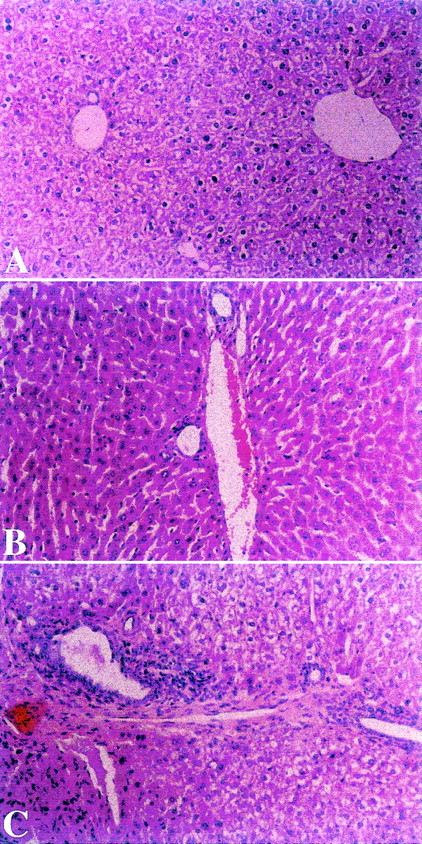

Alleviation of cGVHD of small bowel by oral tolerance.

Small bowel biopsies were performed in all mice from all experimental and control groups 52 days after transplantation. Significant alleviation of all parameters was observed in mice from experimental group A fed with homogenates of splenocytes derived from recipient strain BALB/c mice (Figure 4A). In contrast, biopsy specimens from control nontolerant recipients in groups B and C, fed with homogenates prepared from syngeneic B10.D2 mouse splenocytes or BSA, respectively, manifested severe mucosal damage, distortion of villous architecture, reduction in the number of mucosal cells and crypt hyperplasia, mononuclear cell infiltration within the lamina propria, and cryptitis (Figure 4B and C). With the use of the standardized score grading for bowel involvement in cGVHD, the sum scores for small bowel involvement in groups A, B, and C measured 2.10 ± 0.74 versus 3.17 ± 0.52 and 2.67 ± 0.75, respectively (group A vs group B,P < .002; group A vs group C, P < .005).

Effect of toleration on histologic evaluation of small bowel in transplant recipients.

Small bowel biopsies were performed in all groups 52 days after transplantation. Alleviation of all histologic parameters of cGVHD was observed in mice from experimental group A fed with homogenates of splenocytes derived from recipient strain BALB/c mice (panel A). In contrast, biopsy specimens from control nontolerant recipients in group B and C, which were fed with homogenates prepared from syngeneic B10.D2 mouse splenocytes or BSA, respectively, manifested mucosal damage, distortion of villous architecture, reduction in the number of mucosal cells and crypt hyperplasia, mononuclear cell infiltration within the lamina propria, and cryptitis (Panels B and C). (HαE, original magnification ×10.)